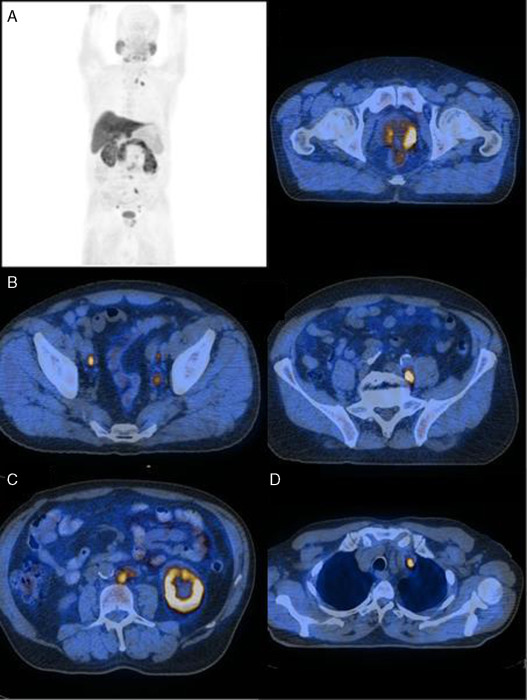

Nas Figura 1 , Figura 2 , Figura 3  ;  Figura 4 apresentam‐se 4 exames PET/CT com FCH‐F18 realizados em contexto de estadiamento inicial de CaP. Na figura 1 encontra‐se um doente apenas com doença prostática com PSA de estadiamento de 48 ng/mL. Na figura 2 apresenta‐se um doente com doença prostática e metastização ganglionar pélvica com PSA de estadiamento de 40 ng/mL. Na figura 3 , o doente apresentava doença prostática e metastização ganglionar à distância e tinha um PSA de estadiamento de 43 ng/mL. Na figura 4 o doente apresenta doença prostática e metastização óssea, e tinha uma PSA de 11 ng/mL.

Doente com CaP com PSA de 43ng/mL, com doença prostática (A) e metastização ...

Figura 3.

Doente com CaP com PSA de 43 ng/mL, com doença prostática (A) e metastização ganglionar, pélvica (B) abdominal (C) e mediastínica (D).